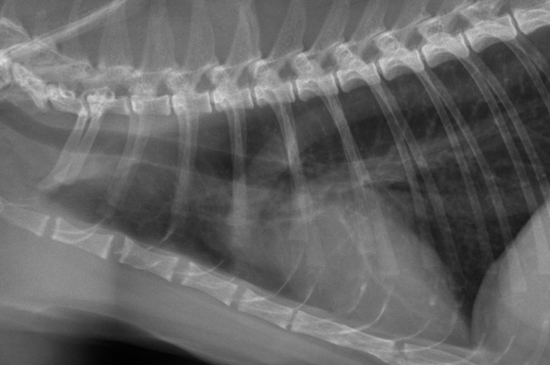

Les patterns pulmonaires à la radiographie

Les maladies pulmonaires chez le chien et le chat se traduisent généralement par une augmentation ou une diminution de l'opacité radiographique des poumons. Ces changements d’opacité donnent lieu à une catégorisation sous forme de « pattern pulmonaire ». Découvrez comment identifier les différents patterns dans cet article !